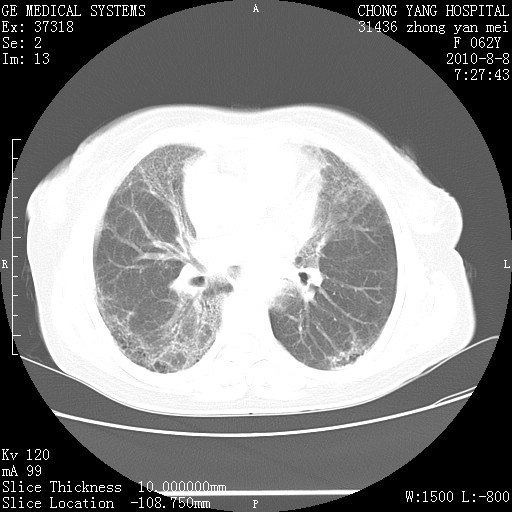

标题: CT28269:F62Y咳嗽胸痛数月。 [打印本页]

标题: CT28269:F62Y咳嗽胸痛数月。

两肺弥漫性间质纤维化伴继发性支扩。

考虑特发性肺间质纤维化

考虑两肺间质性肺炎并肺间质纤维化。

双肺间质纤维化合并感染、肺气肿

双肺间质纤维化

两肺间质纤维化并牵拉性细支气管扩张。

考虑两肺间质性肺炎并肺间质纤维化,肺气囊形成。

两肺间质改变,纵隔淋巴结肿大,需要考虑结节病的可能。